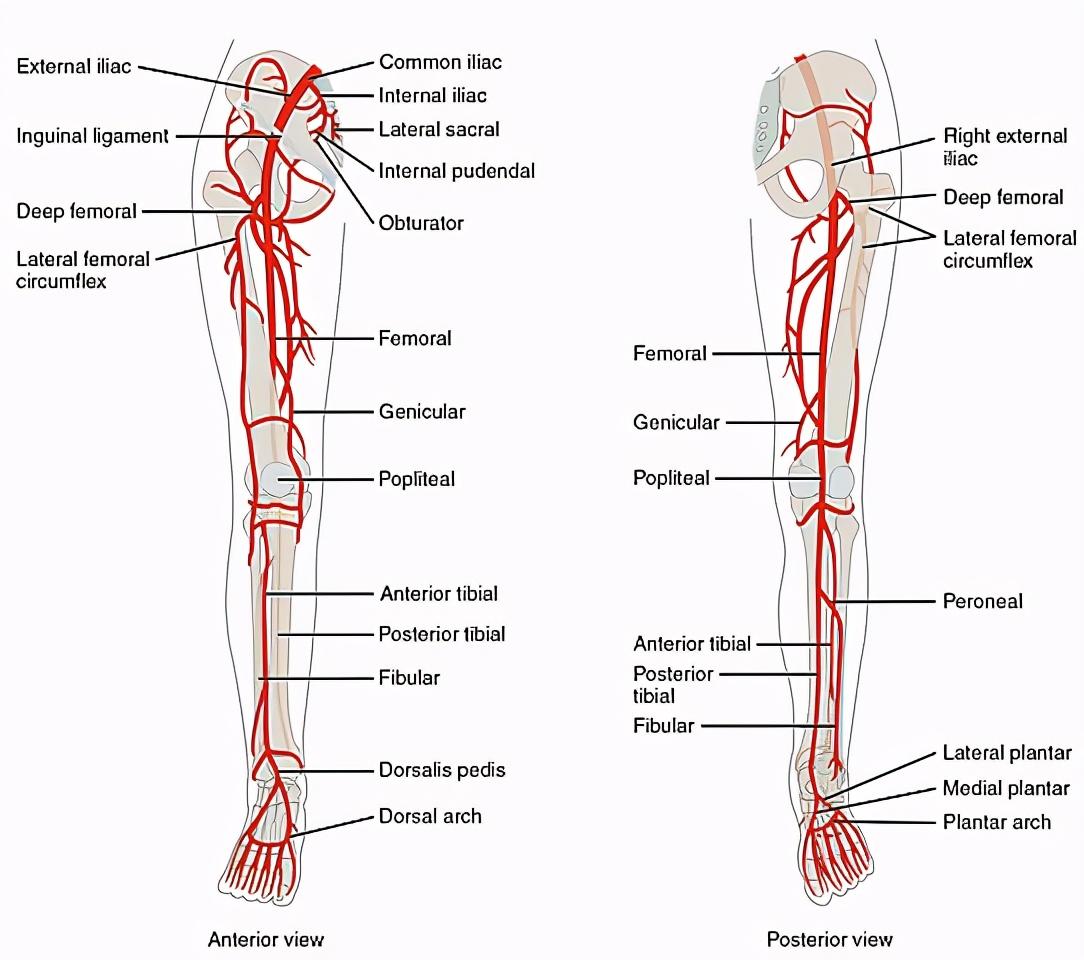

三、腿凉,一走路就疼:下肢动脉闭塞。

很多中老年人同时会伴有高血压,高血脂和糖尿病,在这些问题同时的作用下,就会对血管造成损伤。

特别是有的老年人走一段时间之后,感觉腿疼得特别厉害,需要休息一会儿才能继续行走。

这种情况称之为间歇性跛行,如果间歇性跛行同时还有双下肢发凉,就有可能是下肢的动脉出现了问题。

简单来说就是由于动脉损伤导致了狭窄闭塞,出现了缺血的表现。

我们称这种疾病为下肢动脉闭塞症,往往需要去血管外科看一下是不是严重到需要手术才能治疗。

但是也别怕,并不是所有患者都需要手术。只有步行距离不超过200米的患者才会考虑手术治疗。

另外补充一句,并不是所有的间歇性跛行都是血管的问题,如果没有双下肢的发凉,有可能单纯的是腰椎管狭窄所导致的,这个时候也可以去骨科看一下。